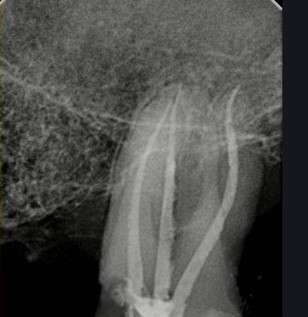

Endodoncija koristimo najnoviju tehnologiju i mašinsku obradu kanala za precizno i efikasno liječenje korenskih kanala, osiguravajući dugotrajne rezultate i očuvanje zuba.

endo time